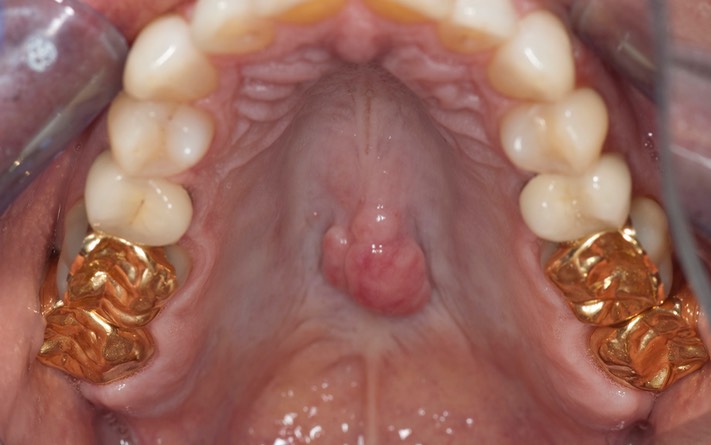

Photos of Clinical Operations

_DSC6148